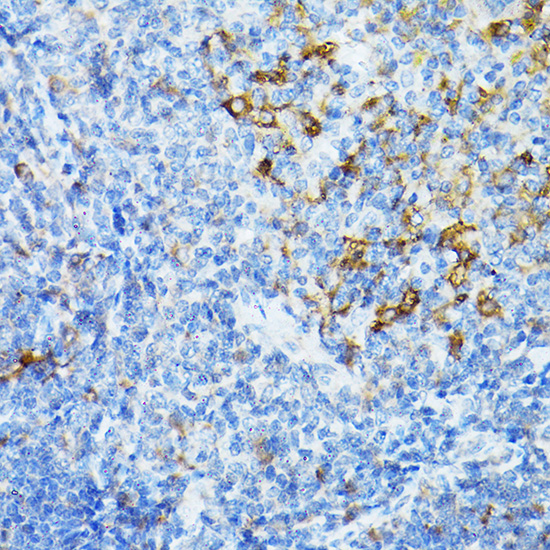

Immunohistochemistry analysis of STING in paraffin-embedded rat spleen using STING pAb at dilution of 1:20 (40x lens).

Immunohistochemistry analysis of STING in paraffin-embedded mouse spleen using STING pAb at dilution of 1:20 (40x lens).